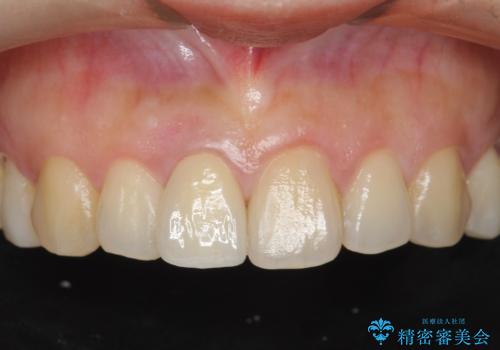

- 30代女性